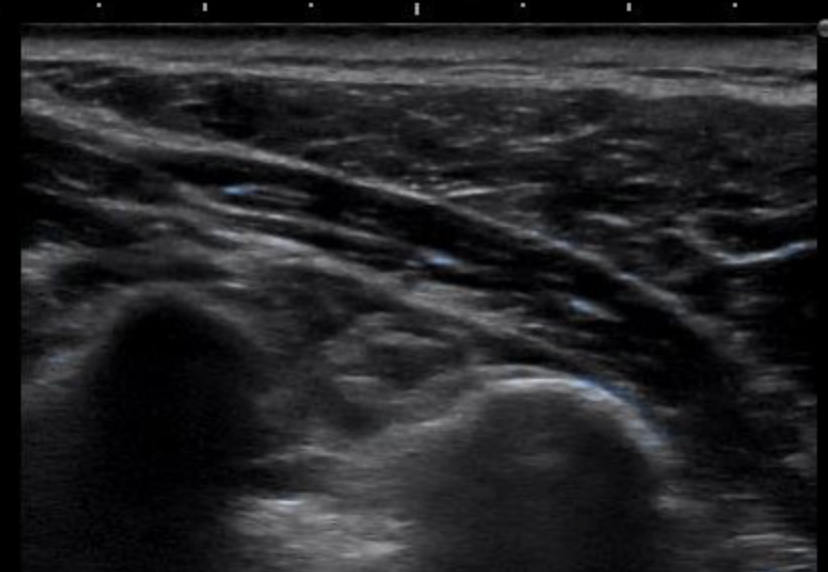

こちらが肩コリを感じていない方のエコー画像です。

両方とも同じような場所をみているのですが、

下の画像の方が、画面下側の白っぽさが強いと思いませんか?

ごく簡易的に説明すると、

エコーは硬いものほど白く映る装置になります。

なので、凝って固くなっている部分が白く厚く映るのではないかということです。

これが肩コリの正体ではないかと考えています。

専門用語で、この白くなった部分をスタッキングファシア(ファシアの重積)といいます。